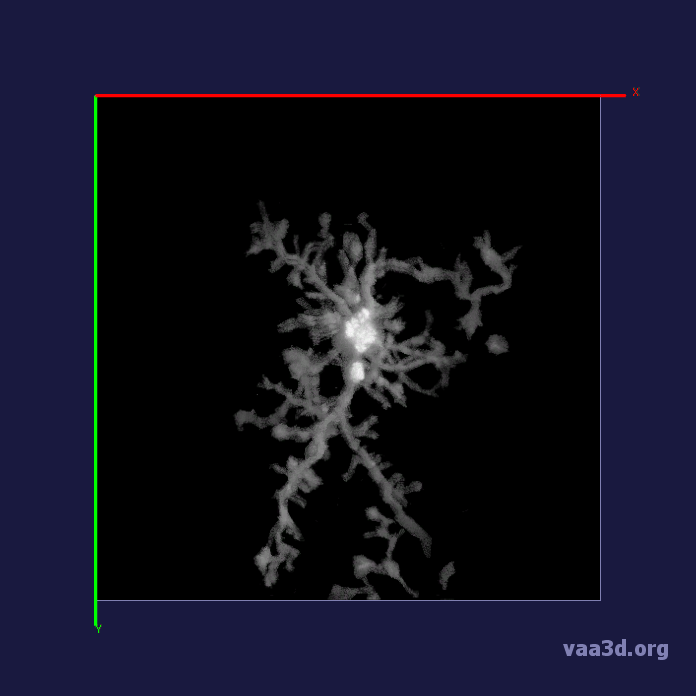

In our experiments, we compare the coupled TuFF-BFF microglia segmentation results with those given by L2S [21] and the Chan-Vese segmentation method [22]. The groundtruth in 3D was attained by manually tracing the object slice by slice from the z-stack. It must be noted that this was done by eye and could have some error. Figure 2 shows the visual comparison of the segmentation results for our dataset. Our result shown on the third column captures both the soma and processes. Figure 3 shows the Dice coefficient comparison of each segmentation method to the ground truth. Since the soma is much larger than the fine processes in the microglia, the processes have less volumetric impact on the similarity score. As explained in Section 1, segmenting the processes is important for quantifying the extension from the soma and its volume of surveillance. We use the Dice coefficient to quantitatively compare the ramification by taking the convex hull of the resulting segmentation. The Dice coefficient is a similarity measure that is computed using with where is the ground truth and is the compared image.

From Figure 4, the average Dice score for coupled TuFF-BFF was 0.77, compared to 0.53 for L2S [21] and .58 for Chan-Vese [22]. It must be noted that L2S required manual user initialization for each 2D image in the stack. While the Chan-Vese method has automatic seed selection, our coupled TuFF/BFF method was the only method that was a true 3D segmentation algorithm. L2S could not consistently capture the entire processes due to the intensity inhomogeneity throughout the object and background noise. The Chan-Vese segmentation could capture the extensions of the processes but did not work well with noise and attained false positives in the reconstruction. Since our method uses the tubular and blob information of the object to separate foreground and background, the segmentation only evolved within the object boundaries.